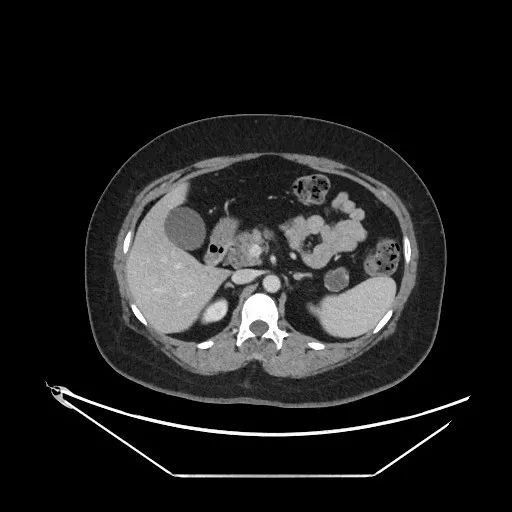

患者刘女士(化名)数月前体检发现胰尾部有一枚肿物,近期就诊上腹部MR增强提示:“胰尾部囊性占位,粘液性囊腺瘤可能”。为进一步治疗,7月27日,患者在家人的陪伴下,赶到广济医院问诊瑞金专家,上海瑞金医院普外科施昱晟教授详细评估后为其制定手术方案。完善术前准备后,施教授专程赴淮,带领东方普外团队顺利完成手术。“从求诊到开刀,专家和先进技术都在淮南解决,免了我们家属奔波之苦,更救了我们家人的命啊!”家属感慨地说。